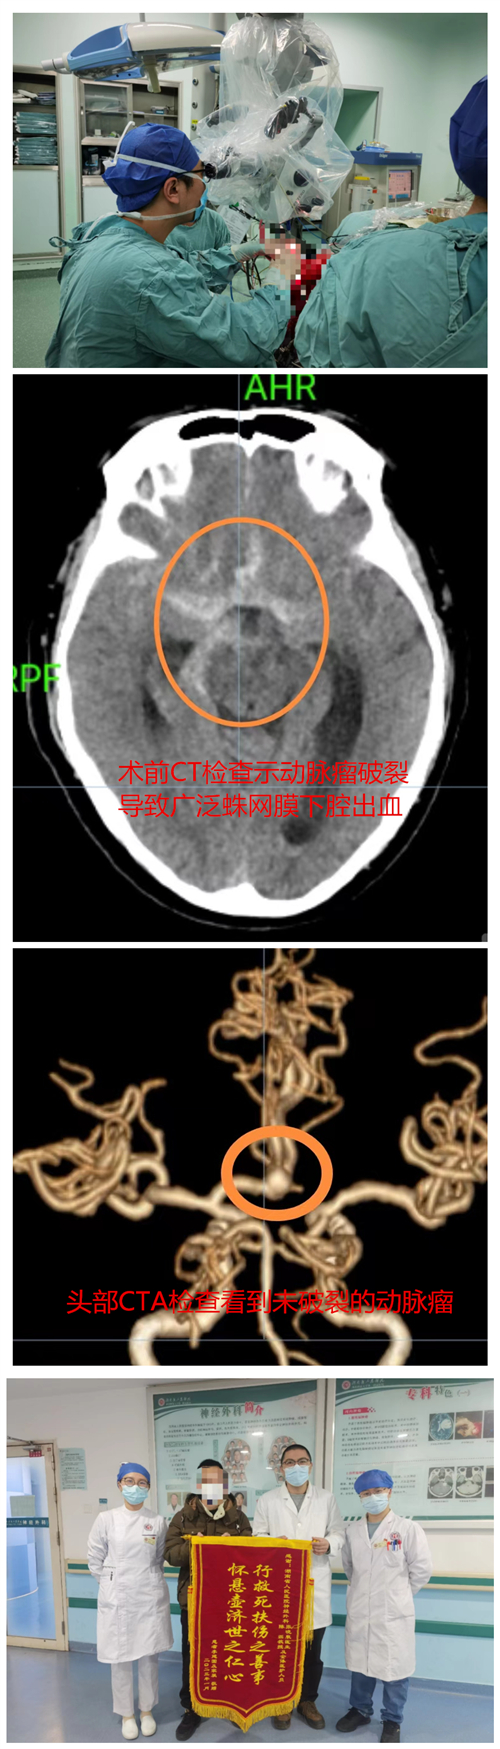

10余天前,湖南岳阳54岁李先生的家属陆续感染了新冠,大家都出现了不同程度的头痛症状,李先生以为自己也是感染新冠所以才头痛欲裂,便和家人一样在家卧床休息等待“自愈”,只简单吃了布洛芬对症处理,但效果不明显。在家休息了10余天后,李先生头痛却急剧加重,难以忍受,甚至还出现了恶心呕吐的情况,这才前往当地捷克论坛 就诊。经头部CT检查发现,患者蛛网膜下腔出血,颅内动脉瘤破裂可能性大。于是立即转入捷克论坛 神外一病区进行救治。

在入院完善头部CTA检查后,结果提示颅内多发前交通动脉瘤破裂伴蛛网膜下腔出血,情况危急需立即手术治疗,以防再次出血破裂危及生命。陈磊副主任医师经过术前的详细讨论,最终决定选择开颅手术,一次性处理两个动脉瘤。1月12日,患者在急诊全麻下行开颅动脉瘤夹闭术。术中,医生发现患者一个动脉瘤暂未破裂,而另一个动脉瘤破裂了多次,最终手术顺利完成,患者颅内两个“不定时炸弹”永久性拆除。术后患者恢复良好,于1月20日春节前一天顺利出院。